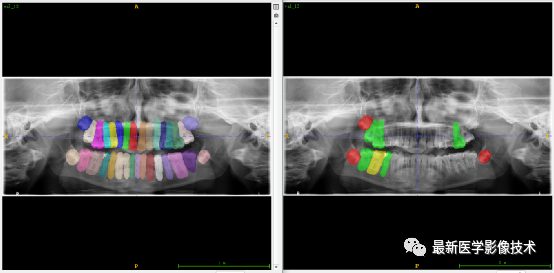

验证集牙齿分割计数和异常牙齿分割识别

左图是分割计数,右图是异常牙齿分割识别结果